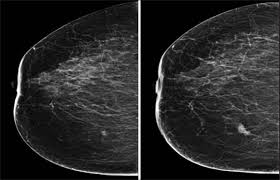

How Does Breast Cancer Look Like On A Mammogram / Mammogram Images Normal Abnormal And Breast Cancer : The outer edges of these cells look fuzzy or spiky (called spiculated).. Healthy mammograms can still vary in appearance. That makes it easy to detect abnormalities, which generally show up as white. If found in an area of rapidly dividing cells or grouped together in a certain way, they may be a sign of dcis or breast. A lump or tumor will show up as a focused white area on a mammogram. Dense breast tissue appears solid.

Breast Masses Cancerous Tumor Or Benign Lump from www.verywellhealth.com Even if you have a lump in only one breast, pictures will be taken of both breasts. This appears most commonly as streaking, known as linear enhancement. A woman's breast tissue also changes over time, and it is not uncommon for benign lumps, cysts or calcifications to form with age. Breast cancer can appear as a spiculated mass, cluster of tiny calcifications, smoothly marginated mass, area of subtle distortion or be invisible on. What does an abnormal mammogram look like? Cancer cells can remain within the milk ducts and this is considered as noninvasive cancer or ductal carcinoma in situ. Magnetic resonance imaging (mri) of the breast — or breast mri — is a test used to detect breast cancer and other abnormalities in the breast. The appearance of normal breast tissue on a mammogram varies from person to person, and no two mammograms look the same.

Breast Cancer Ge News from www.ge.com Healthy mammograms can still vary in appearance. The dye collection in the breast can also look clumpy or appear in a section of the breast, depending on the involvement of dcis. It can also be used to investigate the cause of breast problems, such as a breast mass, pain and nipple. Cancers may be seen as masses (like a ball, but usually with an irregular shape), areas of asymmetry that resemble normal tissue, calcifications (white specks), and/or areas of architectural distortion (imagine the puckering caused by pulling a thread in a piece of fabric). There are few risks associated with mammography. If you've had a mammogram before, the radiologist should compare your old mammogram to the new one to look for changes. After a mammogram that didn't show anything, and a sonogram that found the lump, i was diagnosed with stage 2 breast cancer. The doctor reading your mammogram will be looking for different types of breast changes, such as small white spots called calcifications, larger abnormal areas called masses, and other suspicious areas that could be signs of cancer.

Mammogram Images Normal And Abnormal from www.verywellhealth.com Any area that does not look like normal tissue is a possible cause for concern. The appearance of normal breast tissue on a mammogram varies from person to person, and no two mammograms look the same. A woman's breast tissue also changes over time, and it is not uncommon for benign lumps, cysts or calcifications to form with age. What does cancer look like on a mammogram? Tumors may be benign or cancerous. Abnormalities such as cancerous tumors usually appear brighter because they are denser. Cancers may be seen as masses (like a ball, but usually with an irregular shape), areas of asymmetry that resemble normal tissue, calcifications (white specks), and/or areas of architectural distortion (imagine the puckering caused by pulling a thread in a piece of fabric). Calcifications are calcium deposits within the breast tissue and they look like small white spots.

Any area that does not look like normal tissue is a possible cause for concern. Invasive breast cancer can appear as a white patch or mass on a mammogram. You may notice dimpling or pitting, and the skin on your breast. A rash isn't the only visual symptom of inflammatory breast cancer. The milk ducts carry your breast milk from lobules, where milk is produced, to your nipple. Magnetic resonance imaging (mri) of the breast — or breast mri — is a test used to detect breast cancer and other abnormalities in the breast. A lump or tumor will show up as a focused white area on a mammogram. 1 the gray areas correspond to normal fatty tissue, while the white areas are normal breast tissue with ducts and lobes. A spiculated breast mass, which has spikes extending out from the main mass, is often highly suggestive of cancer. Macrocalcifications, which look like small white dots on a mammogram. It's so important to listen to the messages our bodies are telling. In addition to mammograms, ultrasound and mri may also be used to take a closer look at changes in the breast. Breast cancer can appear as a spiculated mass, cluster of tiny calcifications, smoothly marginated mass, area of subtle distortion or be invisible on.